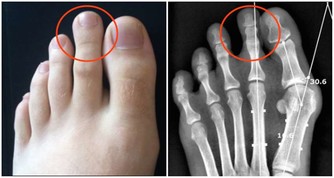

不曉得大家有沒有指甲就會不小心嵌入肉裡的經驗?

以前小時候不太會剪腳趾甲,就很容易會變成這種狀況,

指甲嵌進去肉裡之後就會開始發腫、發炎,甚至還會化膿!

3、正確修剪指甲

使用乾淨的指甲剪,直接適當地剪掉多餘指甲,不要彎曲指甲。如果血液流往足部有障礙,直接請醫生幫忙修剪。

6、修剪指甲到合適的長度指甲剪太短也會造成傷害,記得修剪時留一點點空間。如果指甲太短,可能會在穿鞋時給足部更直接的壓力,導致指甲長進皮膚,最好的長度就是和指尖水平。